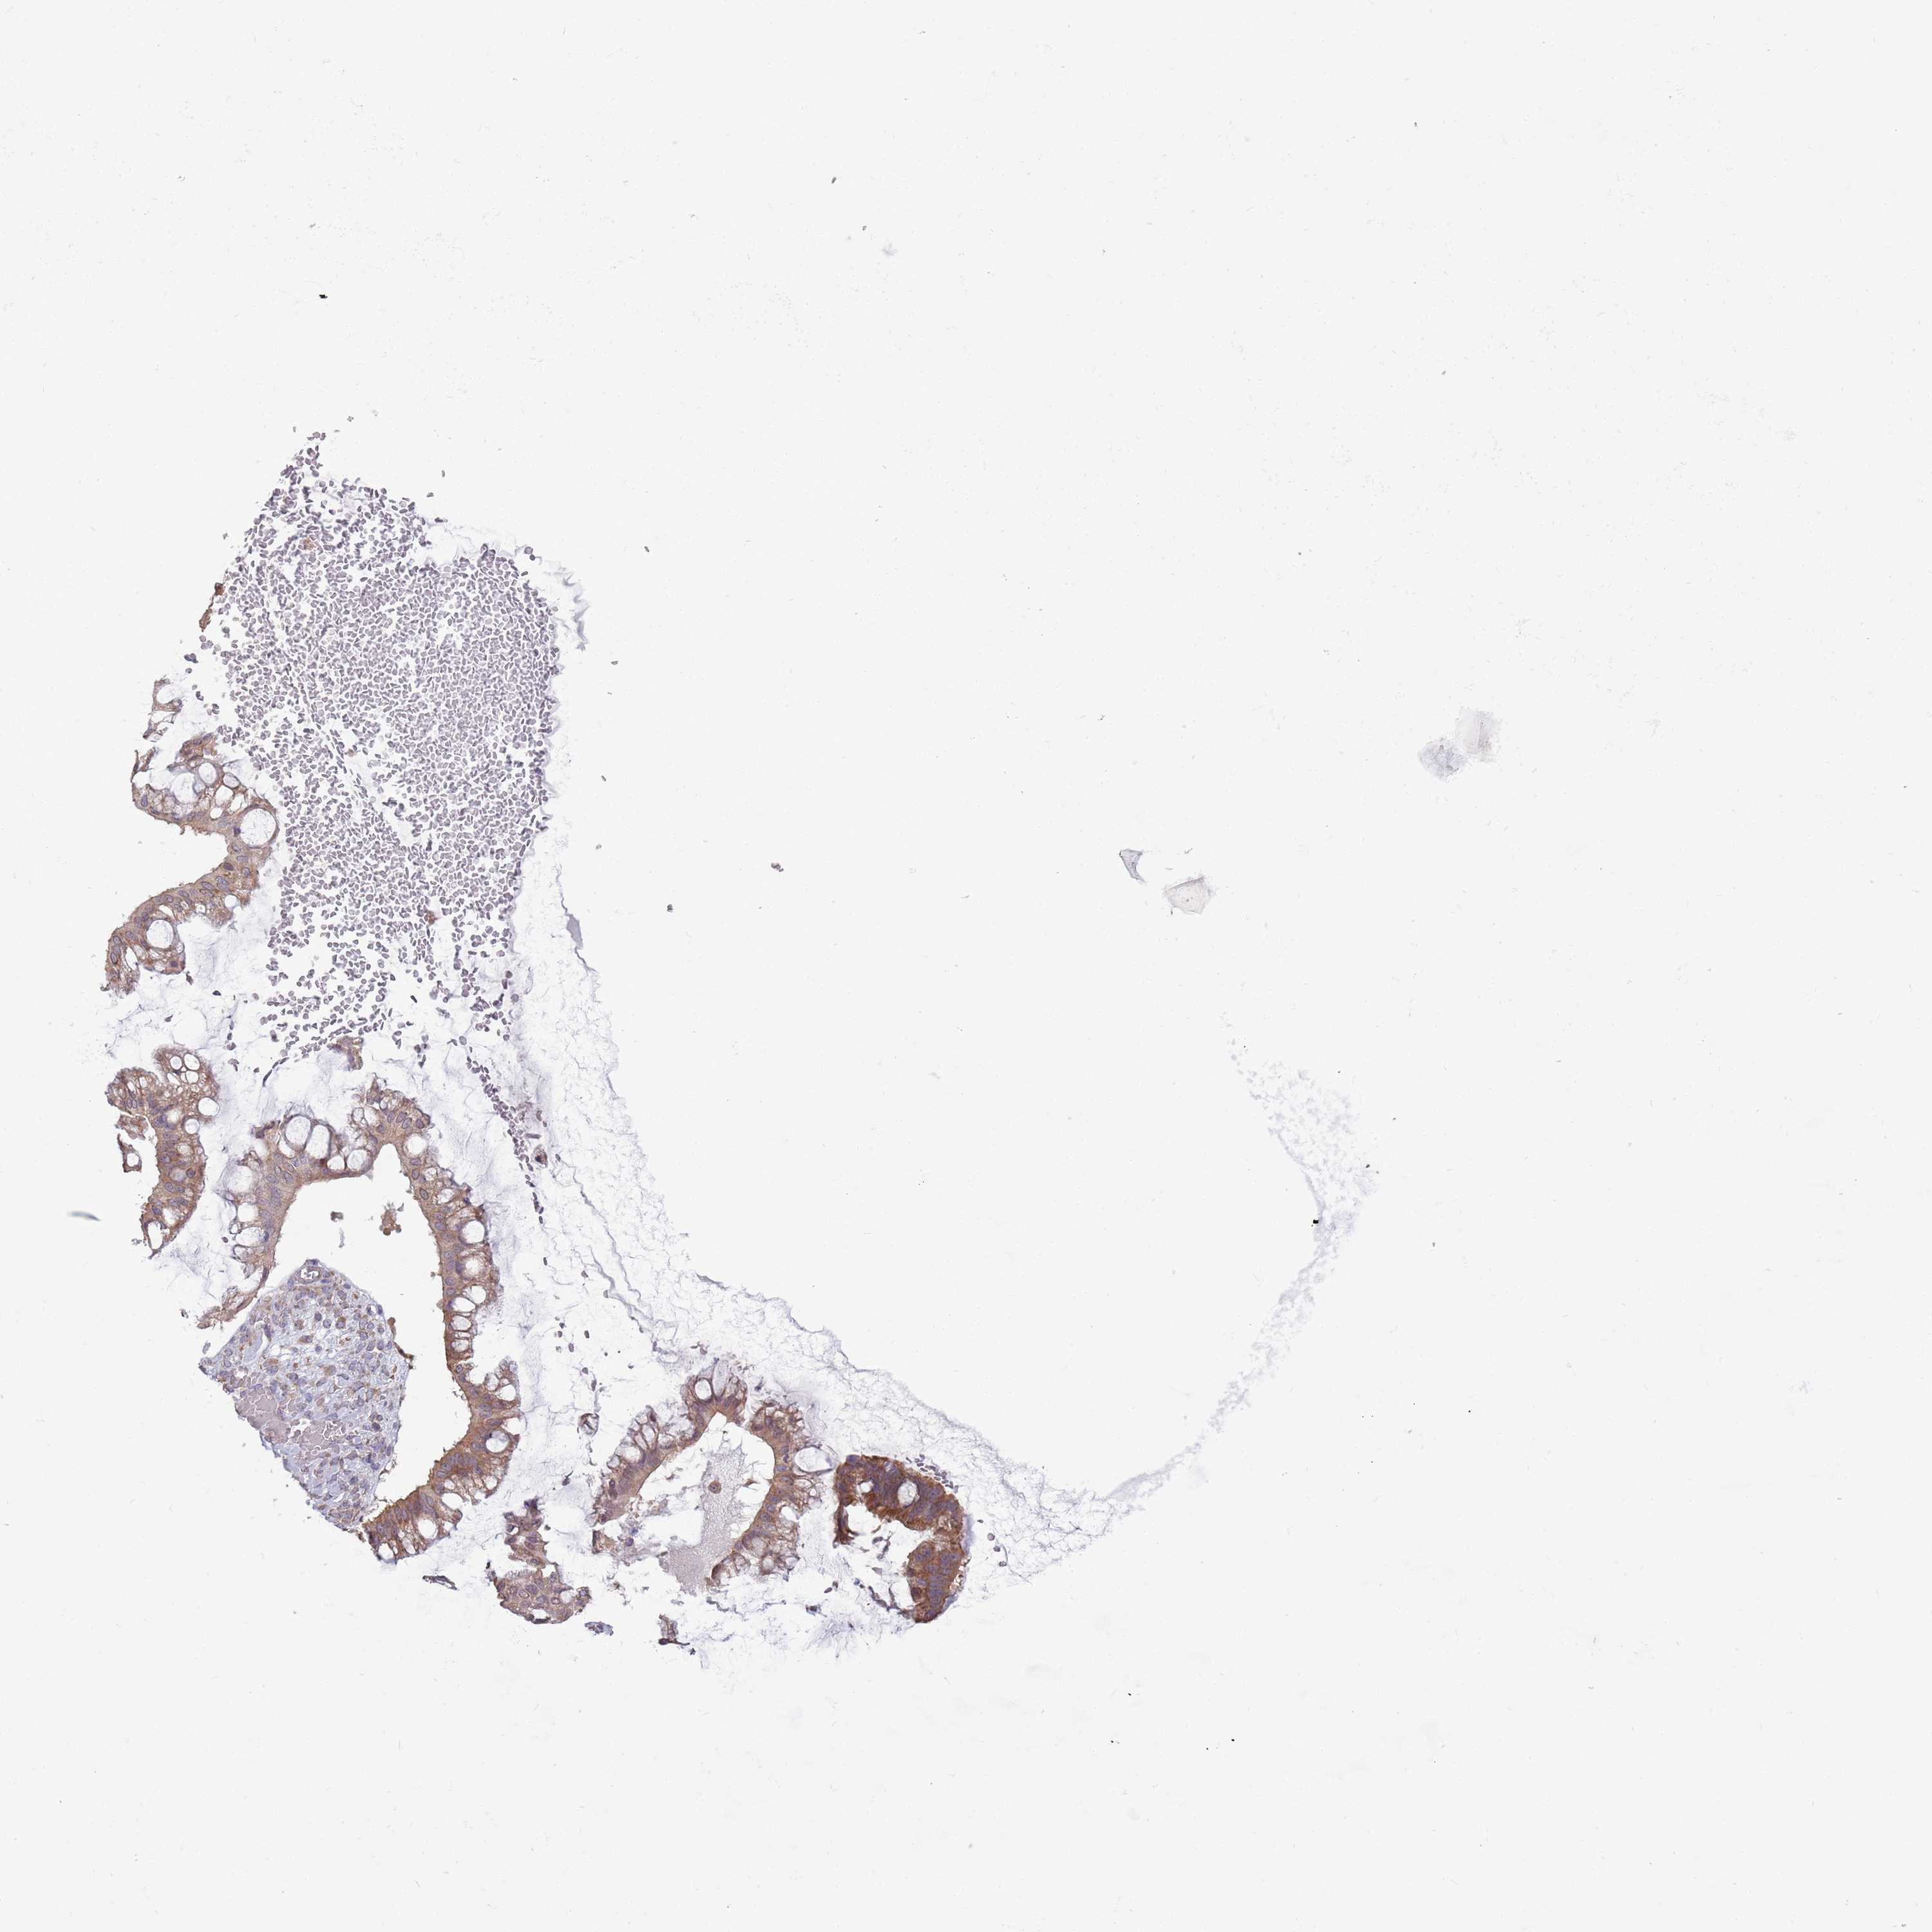

OVARIAN CANCER - Protein expressioni

A mouse-over function shows sample information and annotation data. Click on an image to view it in a full screen mode. Samples can be filtered based on level of antibody staining by selecting one or several of the following categories: high, medium, low and not detected. The assay and annotation is described here.

Note that samples used for immunohistochemistry by the Human Protein Atlas do not correspond to samples in the TCGA dataset.

Antibody stainingi

Antibody staining in the annotated cell types in the current human tissue is reported as not detected, low, medium, or high, based on conventional immunohistochemistry profiling in selected tissues. This score is based on the combination of the staining intensity and fraction of stained cells.

Each image is clickable and will lead to virtual microscopy that enables deeper exploration of all samples and also displays staining intensity scores, fraction scores and subcellular localization as well as patient and tissue information for each sample.

Antibody HPA043724

Antibody HPA046385

Cystadenocarcinoma, serous, NOS

Carcinoma, NOS

Cystadenocarcinoma, mucinous, NOS

Carcinoma, endometroid